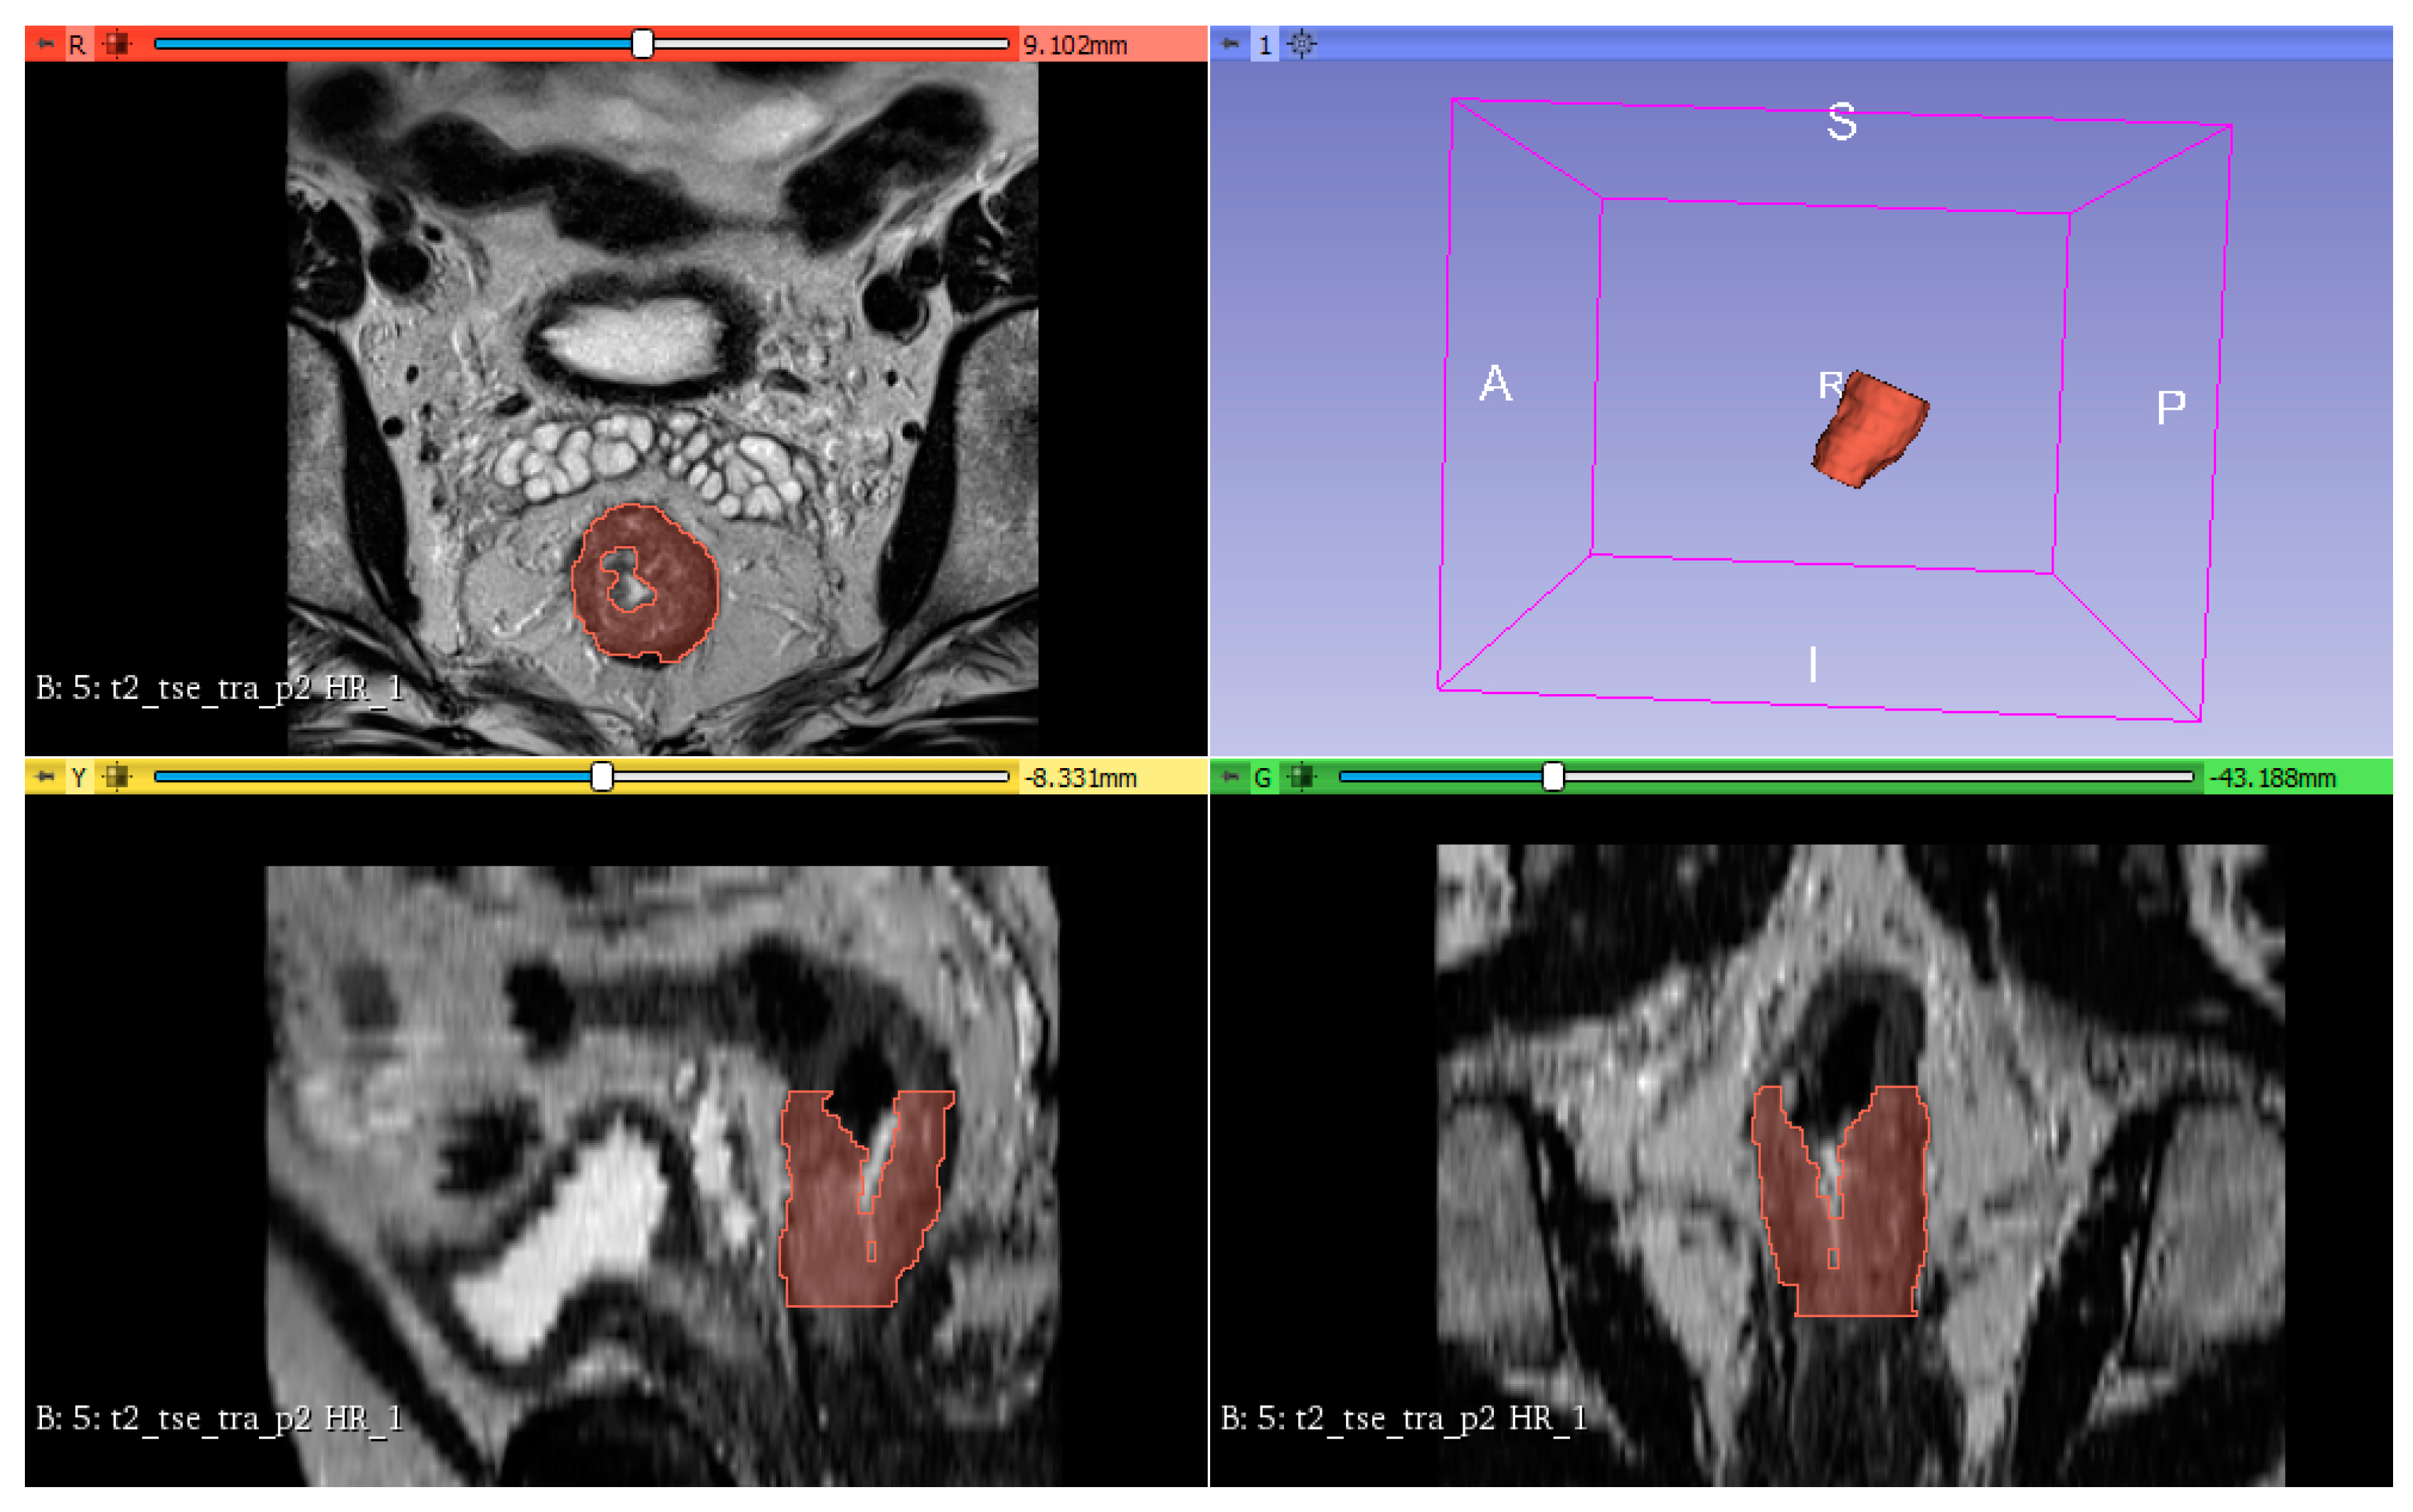

2.1. Patients Characteristics

4.4. Preprocessing, Segmentation and Feature Extraction